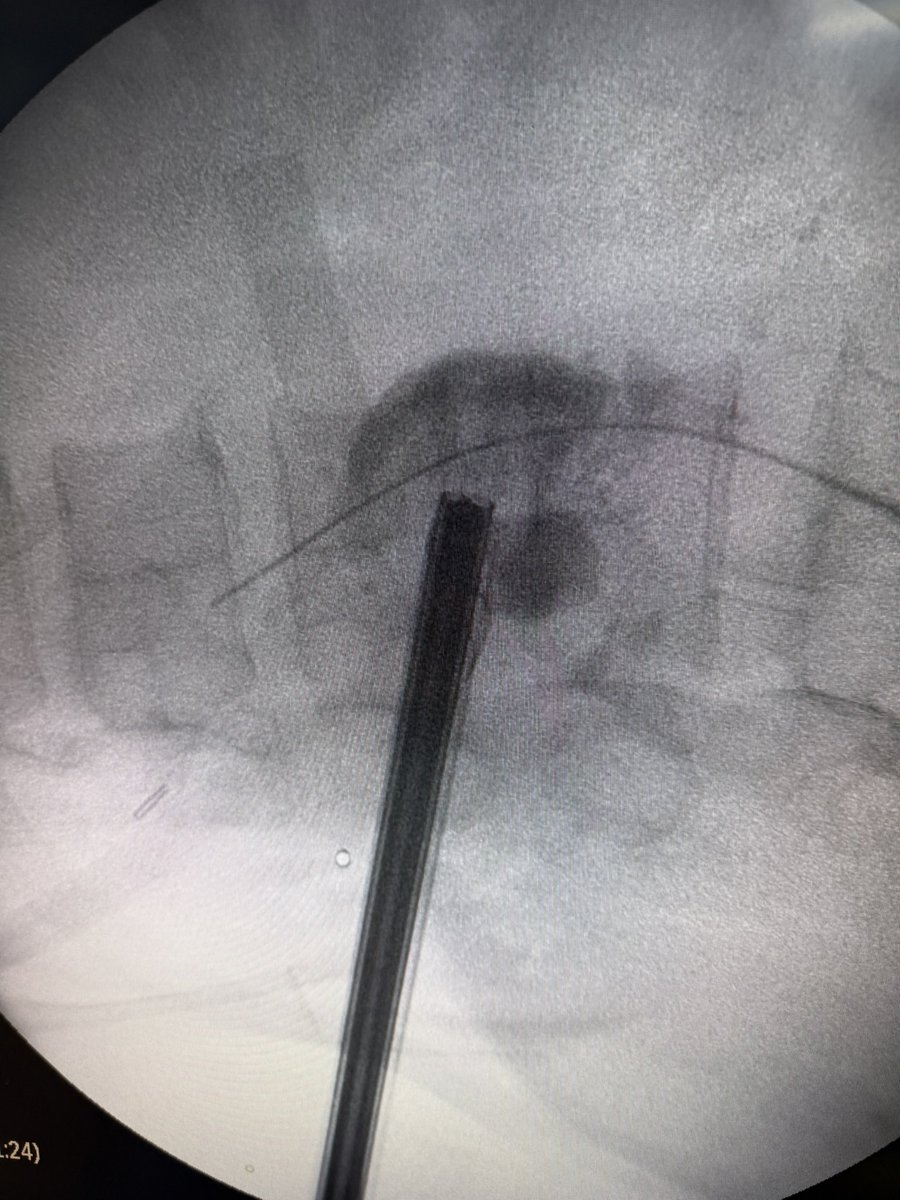

💥 Our Hands-On Course on Ultrasound-Guided PCNL at @CMUN_Urologia was a great success!

An incredible day of practical learning, experience sharing, and passion for advancing minimally invasive surgery